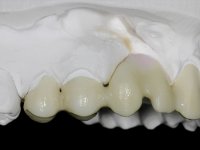

Fixed partial denture between teeth 15 and 11, using teeth 14, 13 and 11 as abutments. Teeth 12 and 15 were planned as ovoid pontics. The framework material chosen was zirconia and the veneering ceramics should have a gum-shade component to rehabilitate the soft-tissues.

After the root canal treatment of tooth 11, dental impressions were taken to do a fixed provisional (reinforced) acrylic prosthesis. The provisional bridge included an acrylic component with a gum-shade color, to evaluate the integration of the treatment plan, in relation to function and esthetics. The preparation of teeth 14 and 13 were minimal invasive, with supra-gingival finishing lines, preserving enamel at its uttermost. Tooth 11 was prepared in a conventional way, with an intra-sulcular margin. The provisional bridge was rebased intra-oral with an autopolymerized acrylic. After 4 weeks, a dental impression with a double mixture technique was done. In the dental lab, CAD-CAM technology was used to produce a zirconia framework. In the provisional bridge, it was noted by the patient, and by ourselves, the need for symmetry in the dimensions and shape of the teeth, in relation to their homologues of the 2nd quadrant. Accordingly, a mirror effect was selected in the CAD design of the framework, to mimic in the prosthetic structure the dimensions and shape of the homologous natural teeth. Framework design included also a small zirconia wing covering the palatal surface of the non-prep tooth 21. This wing serves as an additional support and, simultaneously, avoids an eventual occurrence of a future diastema between central incisors. Color selection of teeth and soft-tissues was done by the ceramist in the dental office. After evaluation and approval of the prosthetic work placed in mouth, the dental bridge was bonded. This bonding procedure was optimized by the addition of a zirconia liner in the inner surface of the framework and in the internal surface of the wing. This treatment proved to be esthetically acceptable and functionally able, with a strong contribution to the patient’s self-esteem.